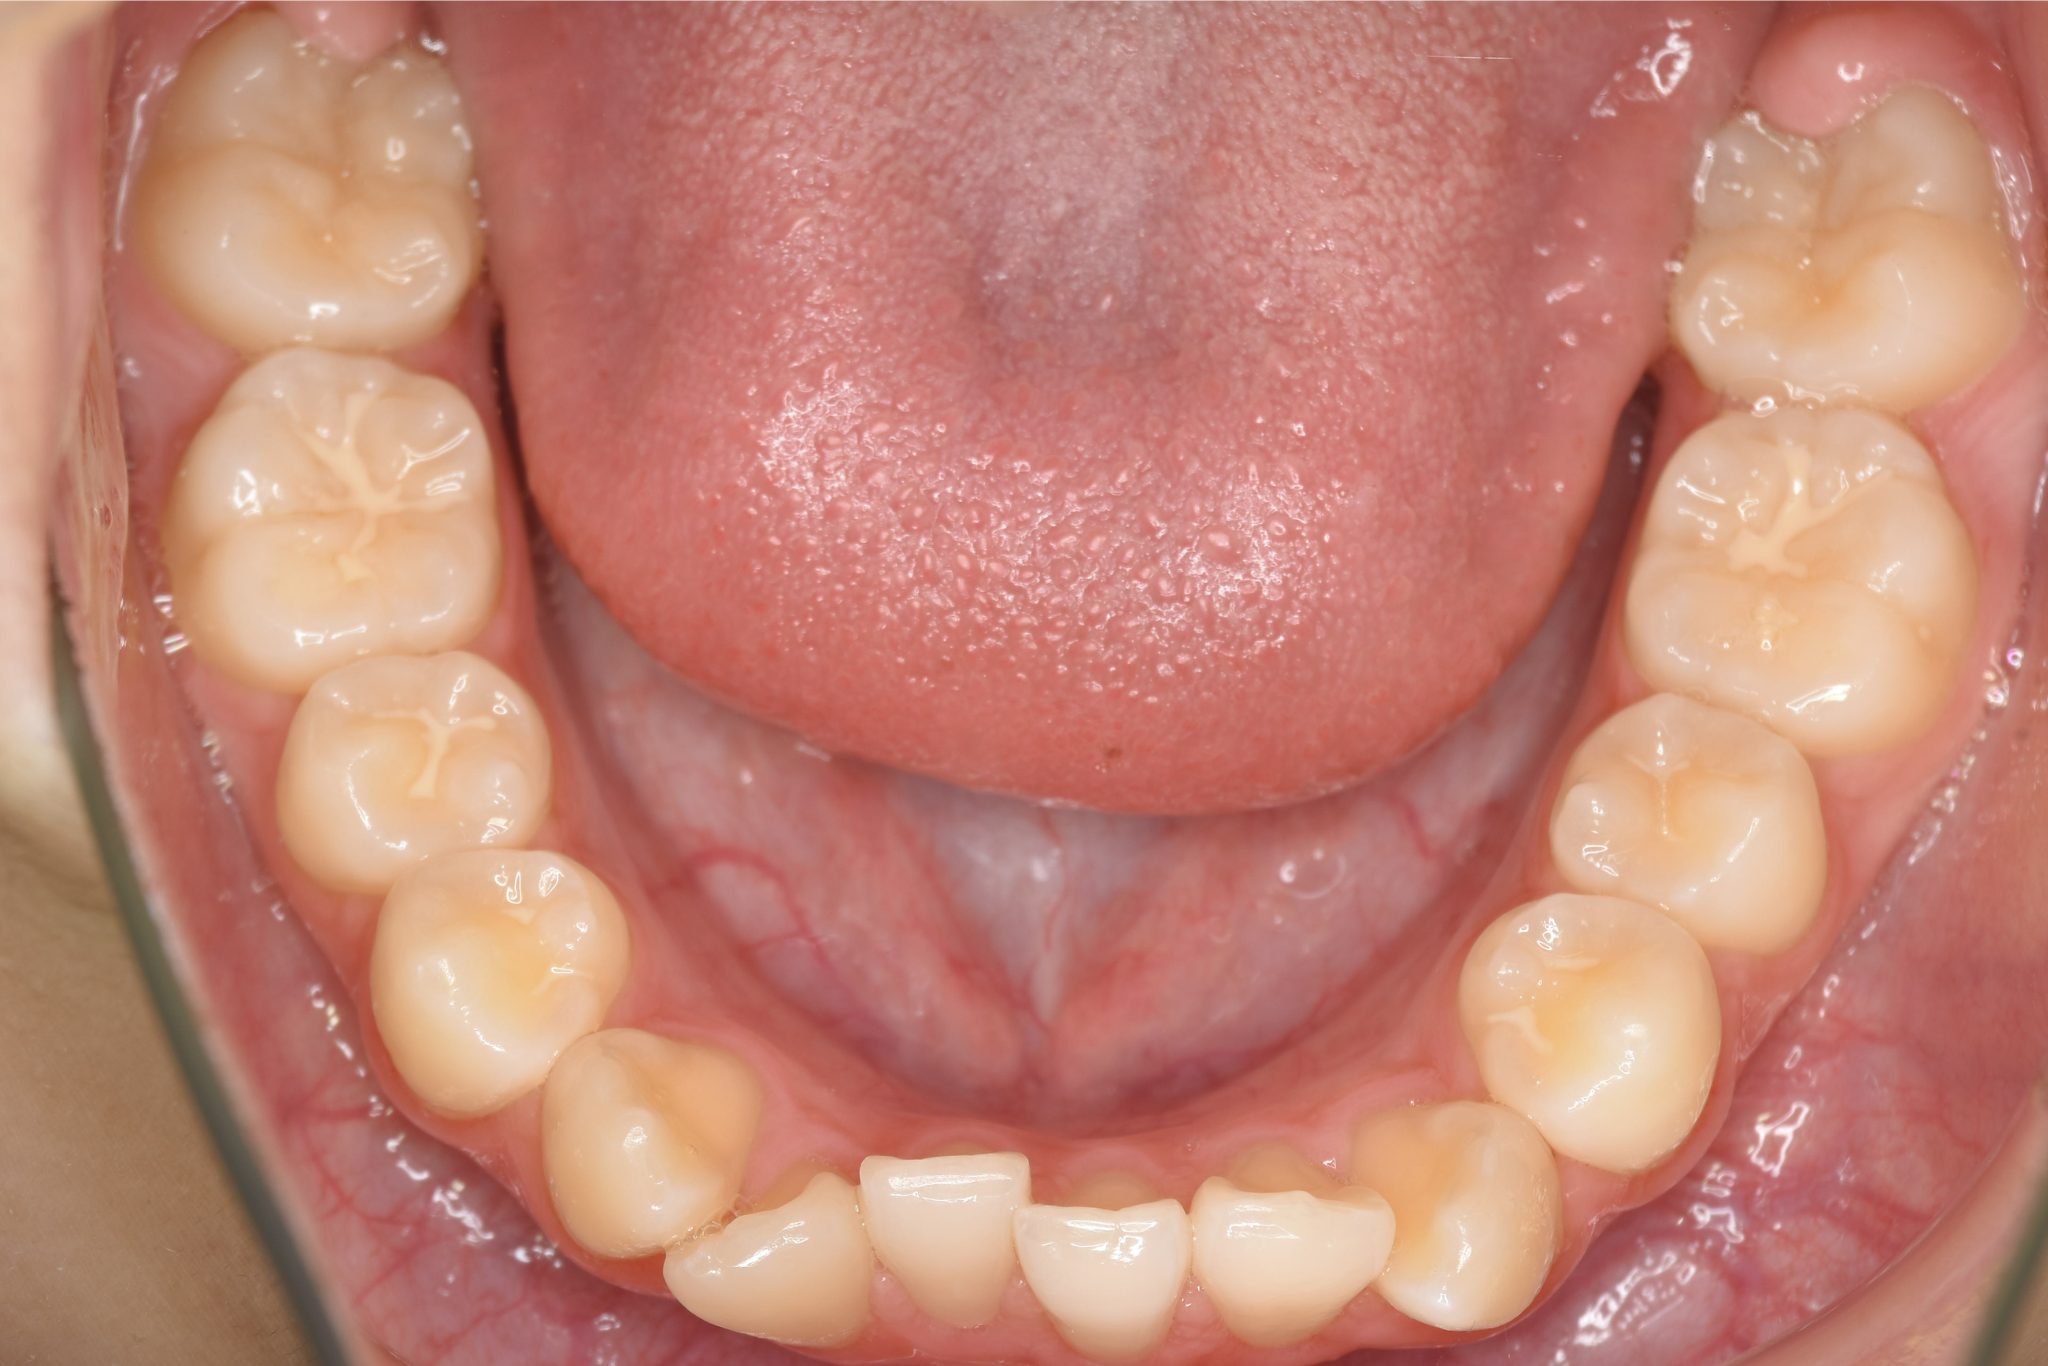

ビフォー

主訴 受け口

施術内容 上顎急速拡大装置と下顎リンガルアーチを用いて上下顎骨を拡大した。

上顎前方牽引装置を用いて上顎骨を前方に成長促進させた。

その後マウスピース型矯正装置で歯牙を配列し良好な咬合を獲得した。

治癒期間 2年9ヶ月間